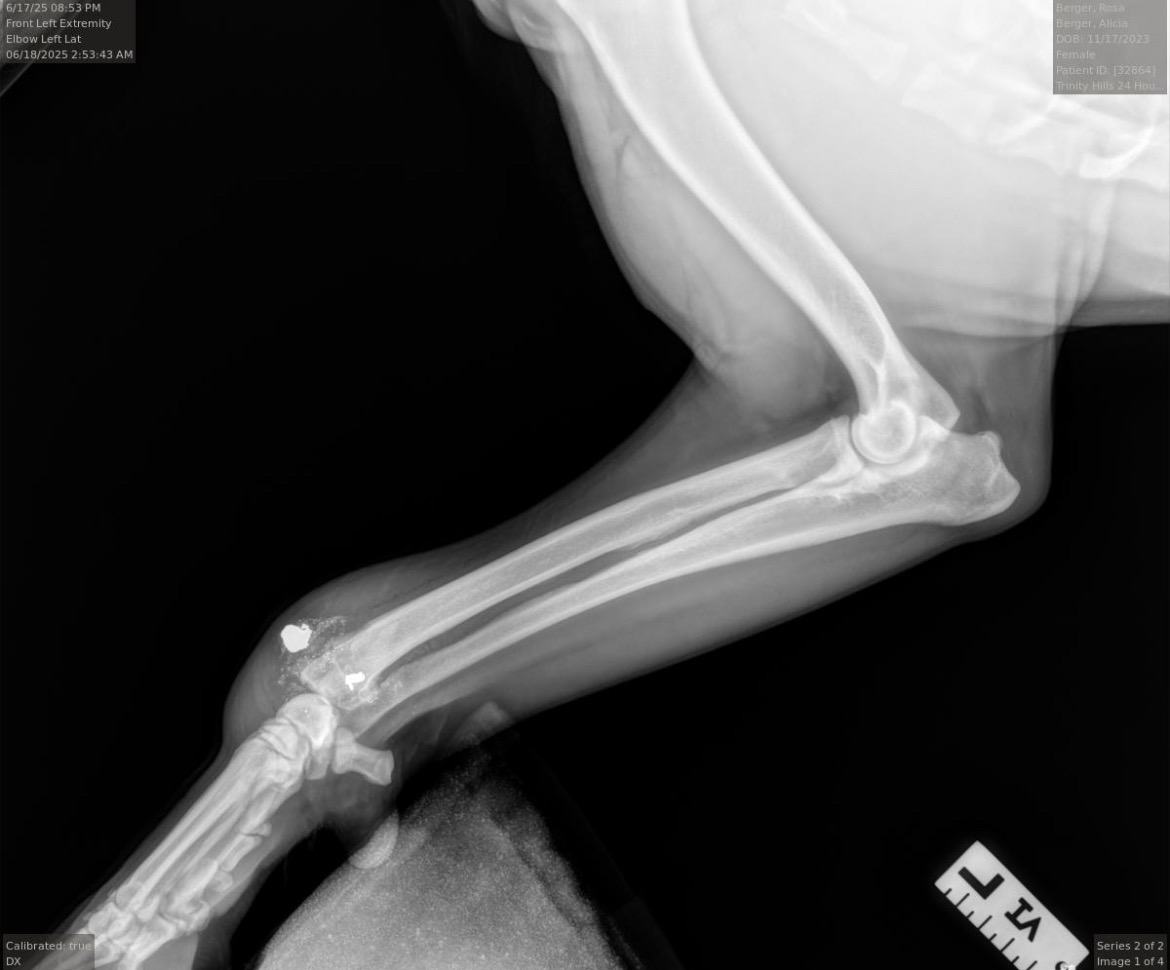

Rosa requires surgery on her leg to remove the bullet and a bullet fragment which is lodged in her bone. She also has a green stick fracture where the bullet fragment struck her leg bone that will need repairs. Rosa is currently at a local emergency animal hospital awaiting an orthopaedic surgeon to perform the necessary procedure.